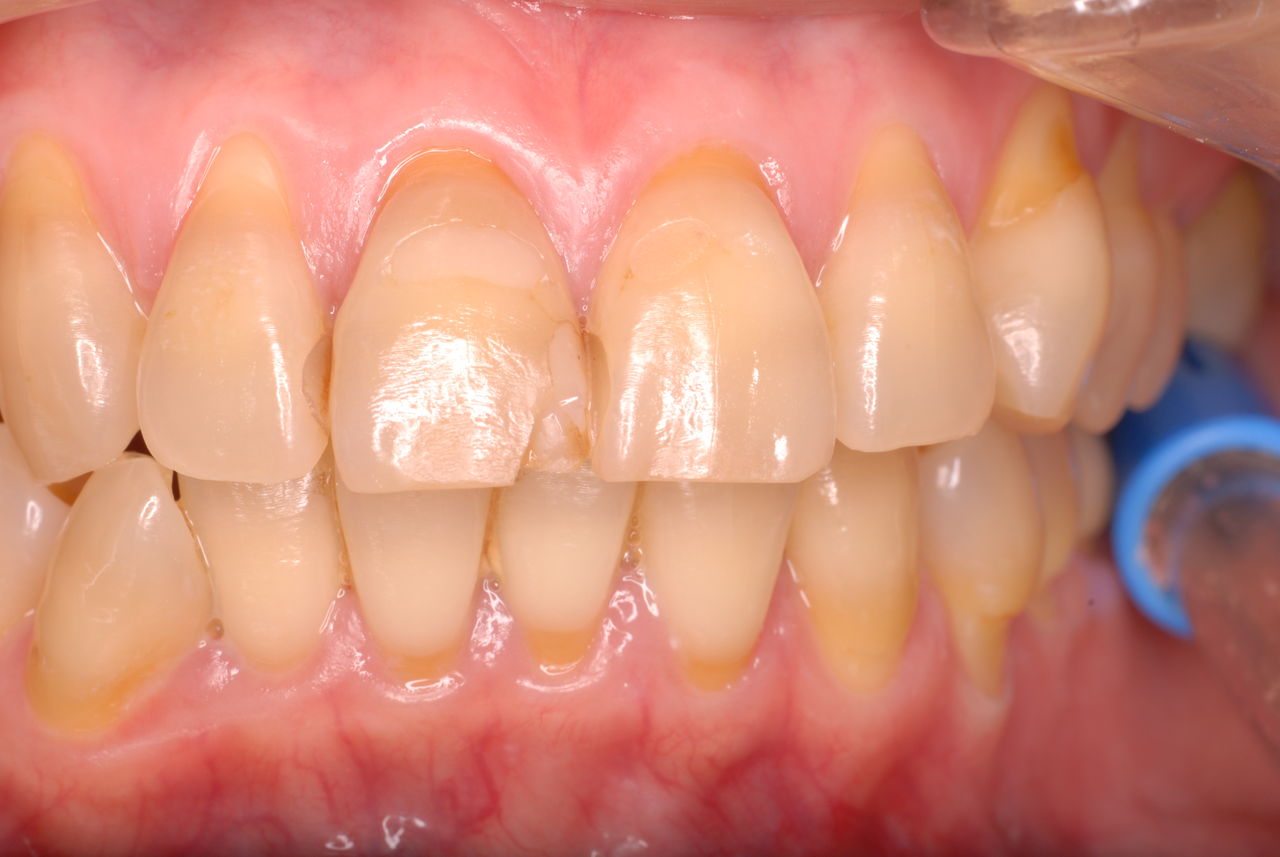

下の歯は数本存在しますが、全て虫歯と歯周病に犯されていました。

食べカスまみれで歯周病に罹患しています。

歯周病になっていましたが、少し色が黄色くなっているだけで比較的綺麗な歯の状態です。